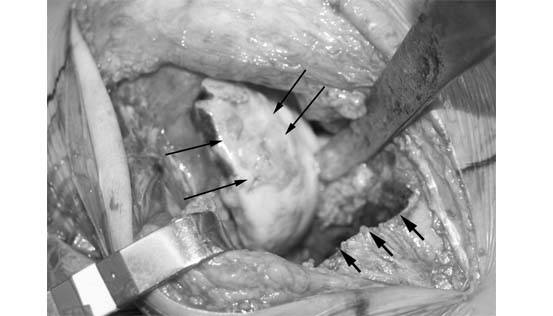

2.She initially was evaluated by arthroscopy and found to have extensive cartilage damage on the tibia and on the femur on the outer aspect of the knee. Her, meniscus was almost completely gone.(large arrows). A probe is being used to feel the cartilage of the lateral tibial surface of the knee. The white flaps are evidence of severe damage to the cartilage (small arrow). Based on these findings, she was offered a fresh osteochondral allograft of both the femur and of the tibial surfaces.

4.At the time of the allografting procedure, the end of the femur is found to have extensive articular cartilage damage (long thin arrows). The damaged bone and cartilage of the tibia has been removed at this stage of the surgery. (short arrows).